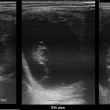

ultrasonografické vyšetření klisny